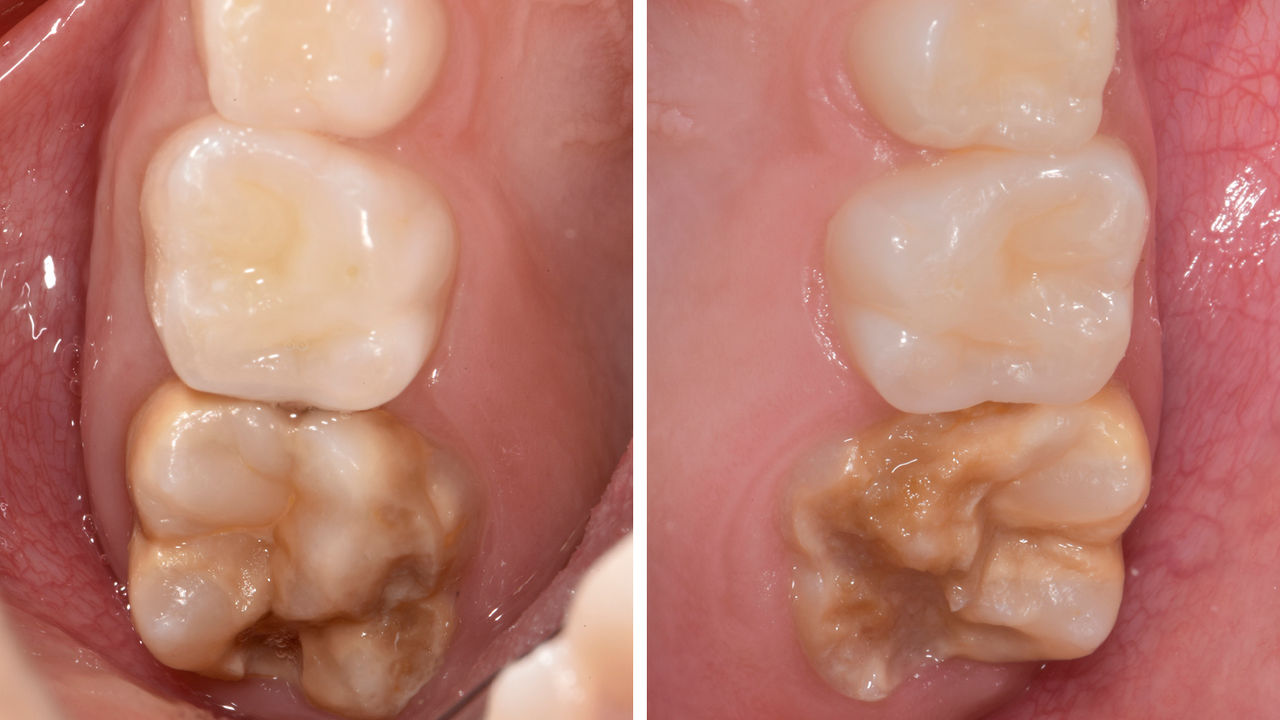

Réhabilitation du quadrant

Deux couronnes CEREC Tessera et deux inlays

En une seule visite de quatre heures, la restauration de deux couronnes et de deux inlays, vieux de 15 ans, a été réalisée. La patient était très satisfaite du très bon résultat esthétique.

Avant : Plombages insuffisants dans le deuxième quadrant. Les restaurations avaient environ 15 ans.

Après : Couronnes fabriquées en consultation à partir du CEREC Tessera (dents 26/27). Inlays pour les dents 24 et 25 en blocs de composite.